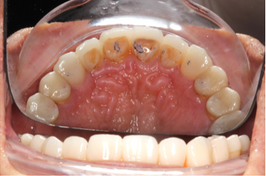

Mr NK, a 52-year-old male, presented with concerns of gradually shortening teeth and sensitivity to cold drinks. He also reported feeling self-conscious about his smile in photos. He is medically fit and has been using a night guard for his sleep-related grinding habit for the past year. Clinical examination revealed moderately worn dentition from erosion and attrition, along with mild crowding of the lower anterior incisors.

Intra-Oral Pictures (Before)

- Erosion severity: ACE Class Class III

- Reduced occlusal vertical dimension

- Mild crowding of lower anterior teeth